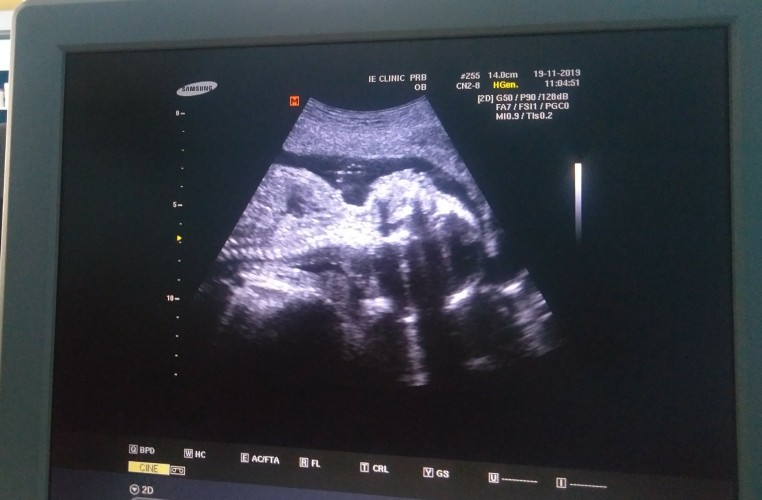

19 week 6วัน ตามเครื่องซาวเลย

ซาวด์น้องตอน 5 เดือน

ของเราตอน 5 เดือนค่ะ